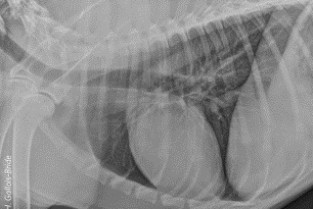

Le GEIM vous propose une séance de travaux pratiques de radiographies sur le thorax. Tous les aspects sont abordés sous la forme de TP de lecture de radiographies numériques sur station de travail Osirix sur tablettes.

- décrire les principes à respecter pour obtenir une radiographie thoracique de bonne qualité ;

- adopter une méthodologie pour interpréter les affections de la cage thoracique, de la plèvre, du médiastin et des poumons chez les carnivores domestiques ;

- décrire l’aspect normal et anormal de la cage thoracique, de la plèvre, du médiastin et des poumons chez les carnivores domestiques.